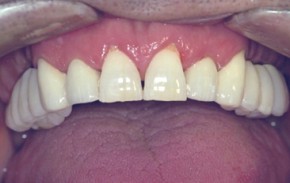

Impianti 1

Agenesia congenita degli incisivi laterali, le due radici naturali erano inesistenti dalla nascita:

- raggiunta la maggiore età, con un apparecchio ortodontico fisso sono stati dapprima leggermente spostati i denti naturali per migliorare la spaziatura a disposizione per i futuri impianti,

- dopo tre mesi di trattamento ortodontico sono stati inseriti due impianti endoossei in anestesia locale,

- dopo altri tre mesi, a consolidamento avvenuto degli impianti (osteointegrazione), sono state posate due corone in ceramica su telaio metallico (elementi fissi),

- il sorriso e la funzione sono stati ripristinati in un modo confortevole.